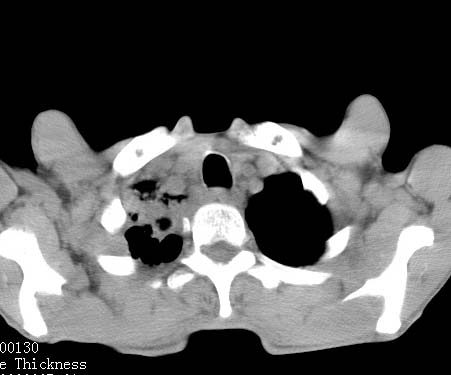

病人女 60岁 咳嗽 气促十余天,大叶性肺炎.

右肺上下叶均见 大片状密度增高影,边界清晰,其内可见支气管充气征,气管支气管通畅。纵膈略向右移位,其内无肿大淋巴结影。首先考虑炎性病变。不排除一些特异性的炎症。不知道发烧吗??wbc高吗??建议治疗后复查!!